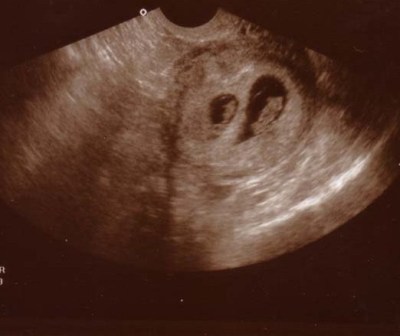

Csöppke!Üdv.a csapatba!Gratulálok mind a kettö bébihez!